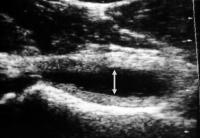

Abbildung 8: Hüftsonogramm bei Coxitis fugax mit Hüftgelenkserguß, dieser als ovale echoarme Zone ventral des starken Echos des Schenkelhalses

deutlich sichtbar.